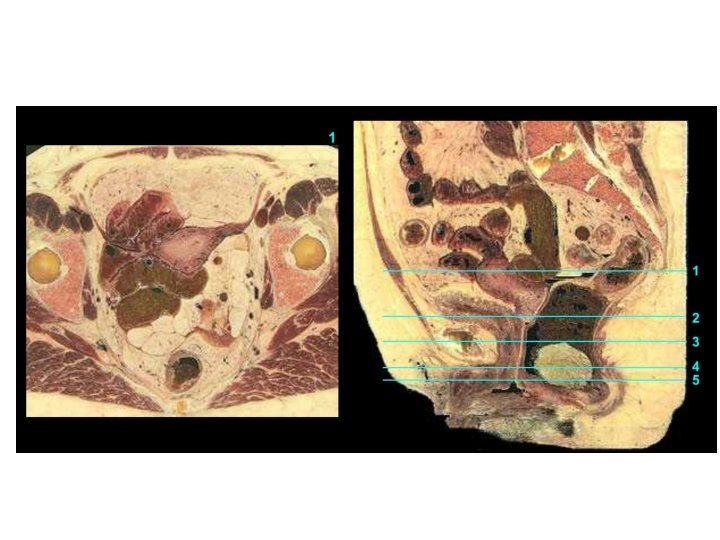

Vagina Excavatio vesicouterina Peritoneum Excavatio rectouterina Uterus Portio vaginalis cervicis Vesica urinaria Portio supravaginalis cervicis Fornix vaginae, Pars posterior Fornix vaginae, Pars anterior Vagina, Paries anterior Rectum Urethra Septum rectovaginale Septum vesicovaginale Vagina, Paries posterior Ostium vaginae Vestibulum vaginae Diaphragma urogenitale